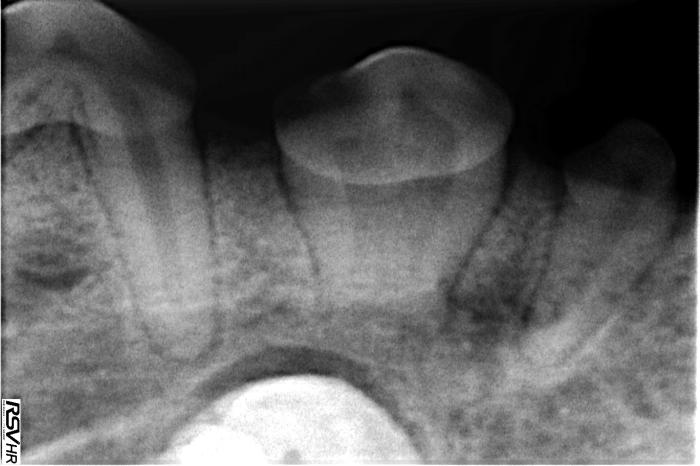

- Presencia del diente 404, incluido en el cuerpo mandibular, ventral a los dientes 406 y 407, con una forma acortada y aberrante (Figuras 5-7).

- Fusión de las raíces del diente 406, sin signos patológicos asociados (ver Figura 5).

El estudio tomográfico permitió confirmar el diagnóstico de las alteraciones detectadas (Figuras 8 y 9).

Además, permitió comprobar la relación del diente 404 con los dientes 405 y 406, hallándose este ventral a ellos y al canal mandibular, estando ventral y medial a él. Se observó también que la silueta en la cara medial y ventral de la mandíbula estaba algo engrosada por la presencia del diente.